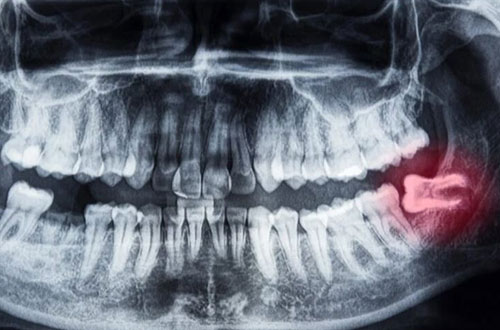

Varför behöver visdomständer opereras?

Ibland kan en operation av visdomstanden krävas och det kan då bero på att omständigheterna kring tanden gör så att den inte går att dra ut. Det kan exempelvis bero på att tanden har vuxit snett, drabbats av en omfattande infektion eller är retinerad, att tanden ligger kvar i käken täck av slemhinna och ibland även ben. Tandens rötter kan även vara böjda vilket gör att det är svårt att dra ut den. I de fall man måste ta bort en visdomstand som sitter komplicerat är operation det bästa alternativet.